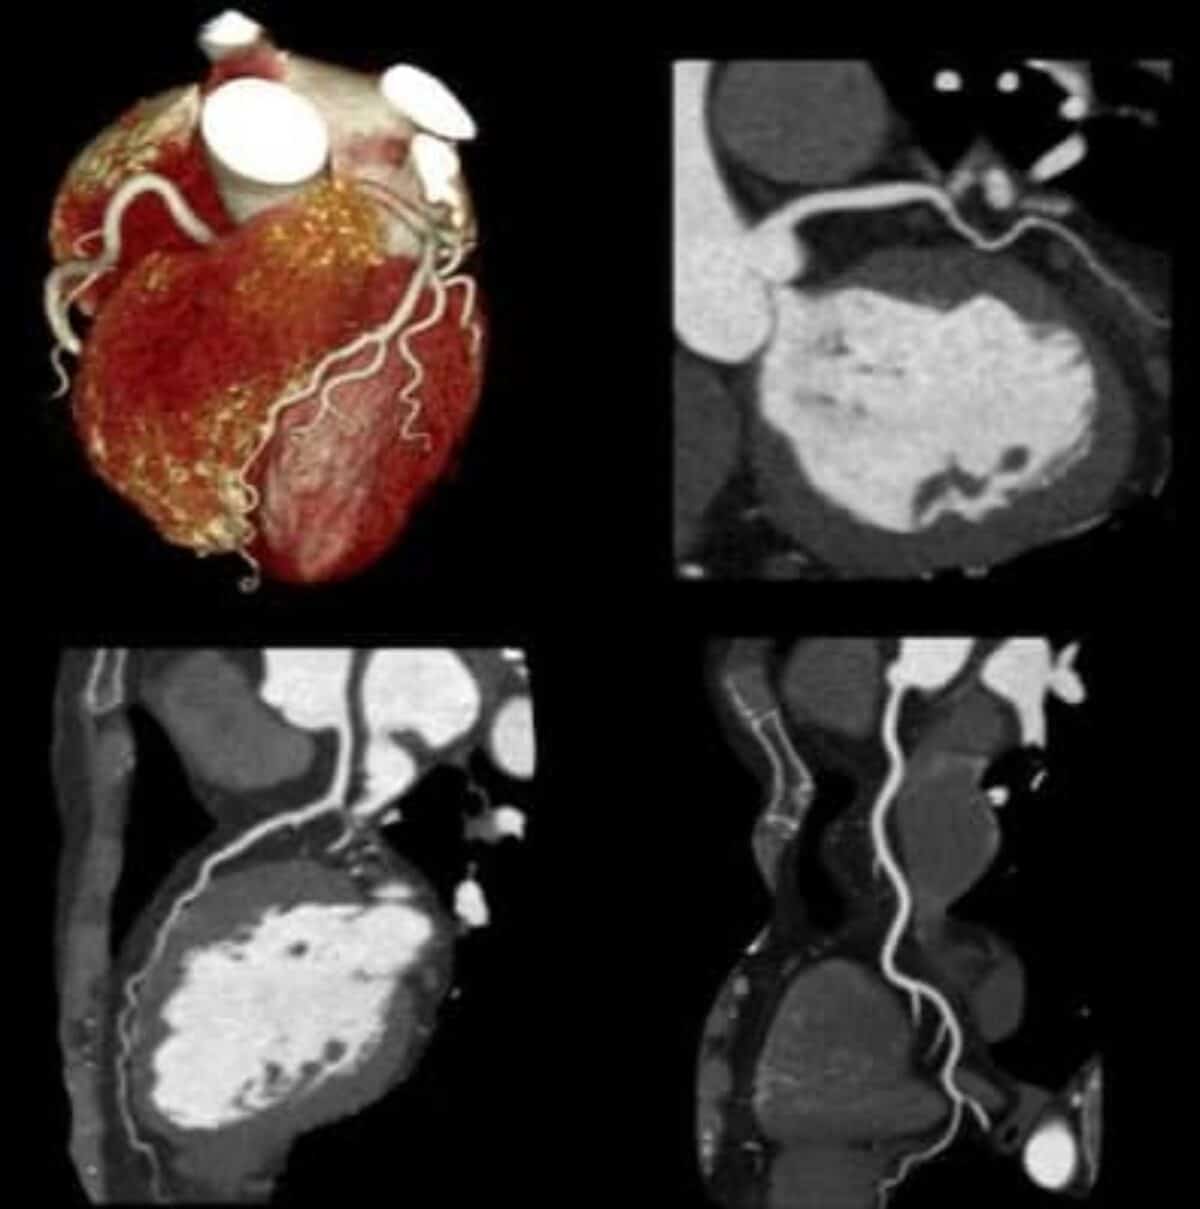

La angiotomografía de coronarias es un método avanzado de imagen cardiovascular útil para valorar la anatomía de las arterias coronarias. Esto es; sin necesidad de realizar un cateterismo cardiaco.

La tomografía cardiaca (angiotac coronaria) combina una técnica especializada de Rayos X y sofisticadas computadoras que producen múltiples imágenes tomográficas del corazón.

La tomografía de corazón permite valorar la anatomía de las arterias coronarias. Tambien, definir si existe obstrucción de las arterias coronarias.